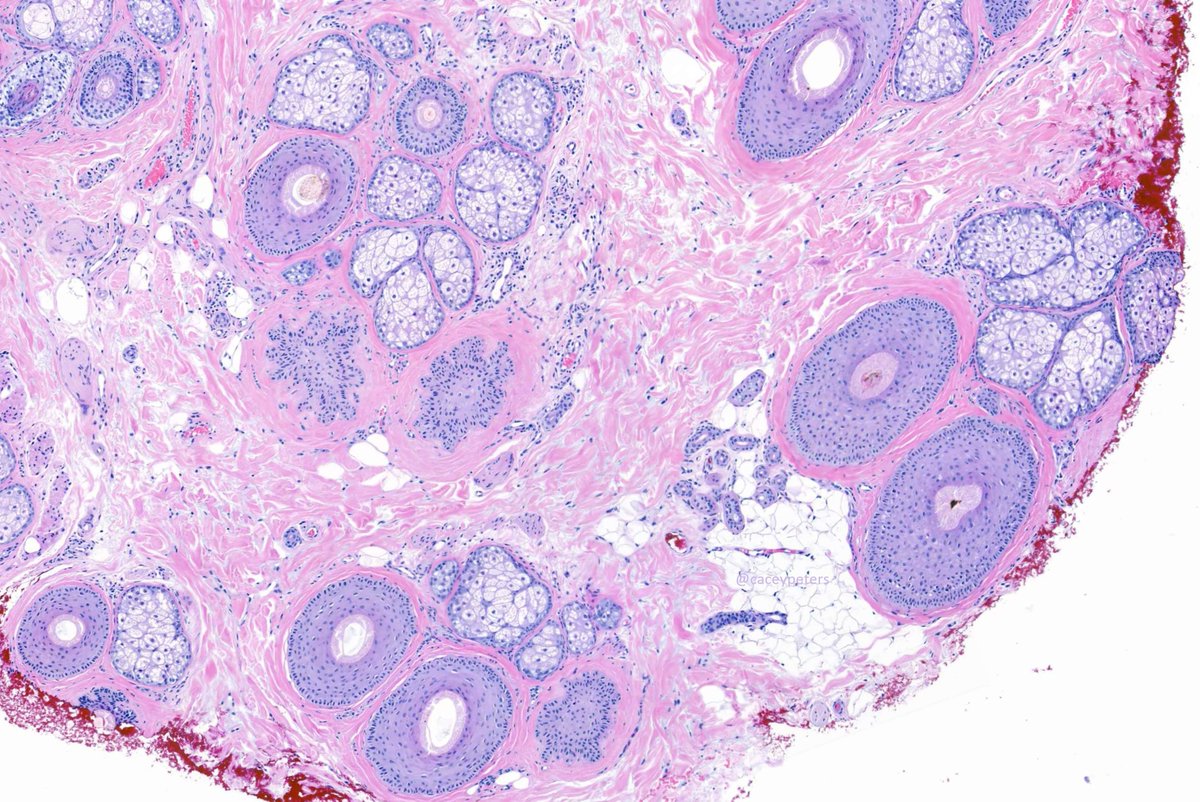

Great example of this entity. Why might this patient be losing their hair? #hair #dermpath #dermatology #dermtwitter #pathology #PathTwitter #MedTwitter #MedEd

Great example of this entity. Why might this patient be losing their hair?

#hair #dermpath #dermatology #dermtwitter #pathology #PathTwitter #MedTwitter #MedEd